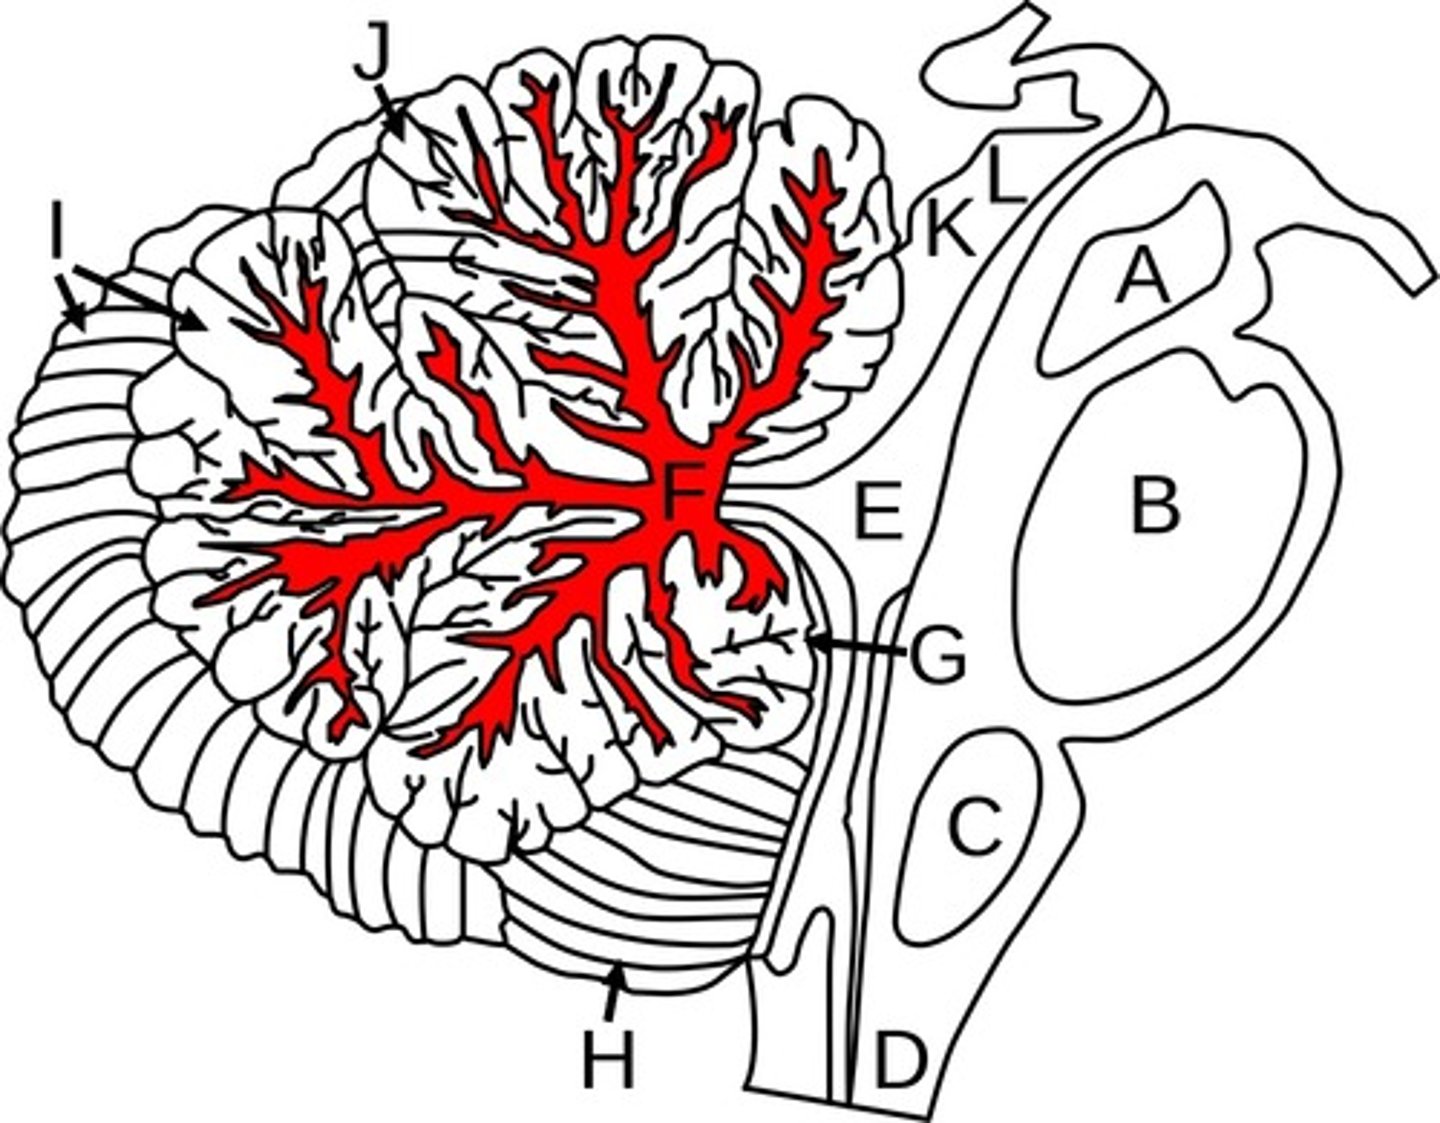

Cerebellum

Arbor Vitae

Cerebellum

-coordinates muscles movements, muscle memory